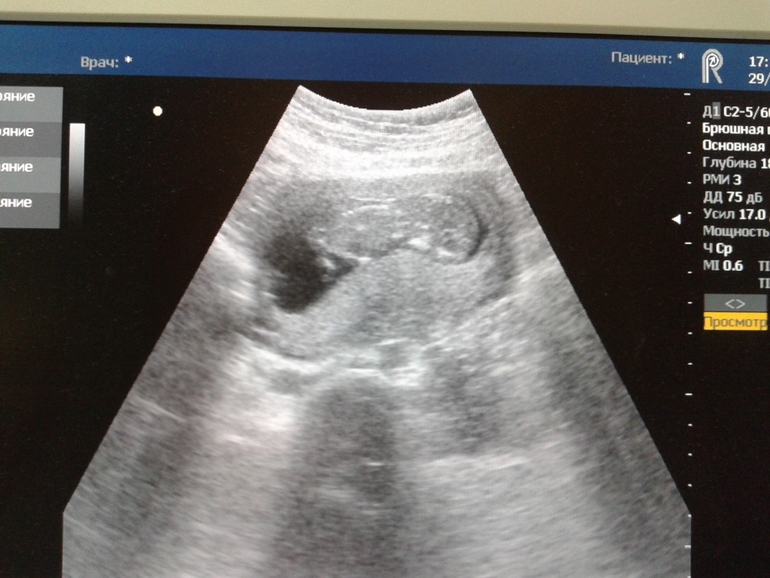

первый скрининг )))

шла, боялась,а зря )узистка говорит, что у меня уж ооооочень активный бэбик ))12,6 недель! )всё там окэй)включала звук, трошки слышно тарахтение сердечка ))а ещё у нас уже есть нос,миллиметр с копейкой ))а на следующей неделе дофига анализов )